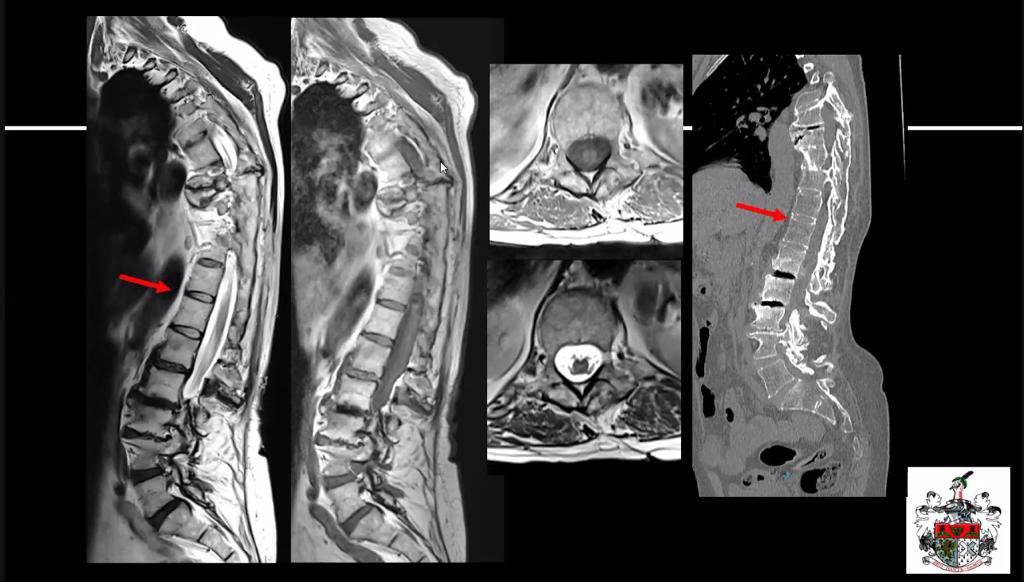

Brilliant comprehensive run through of the tricky post operative spine by @RadheshLalam for @theBSNR educational program for our joint @BSSR_Site session 👏🏾👏🏾 @pacsbin integration and polls- great job!Missed it? Video coming soon 👉🏾 bsnr.org.uk/education/reco… #neurorad #foamrad

Answer:

Subacute combined degeneration due to inhalational abuse

MR: bit.ly/3l6fiSQ 👈Annotated DICOM with notes via @pacsbin

#Radres #Neuroradiology #FOAMrad #FOAMed #NeuroRad #radiology #Radfellow #MedTwitter #Neurology #Spine #Toxicology